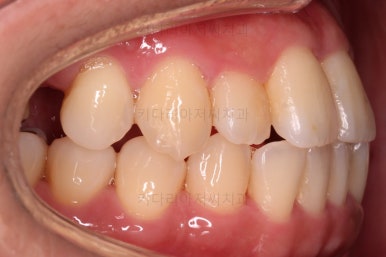

초진 시, 입안의 모습이에요.

앞니의 약간의 틈새, 약간의 삐뚤어짐, 약간의 중앙선 틀어짐 등 심하진 않으나 약간씩의 문제점들이 있네요.

얼굴모습입니다.

약간의 돌출감 특히 아랫입술의 돌출감이 눈에 띄고요.

웃거나 말할 때 약간의 삐뚤어짐과 약간의 틈새가 심미성을 떨어뜨립니다.